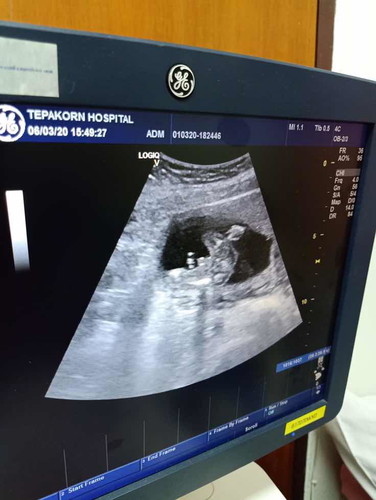

แม่ๆช่วยดูให้หน่อยค่ะว่า ชาย หรือ หญิง

น่าจะชายคะ

ชายค่ะ